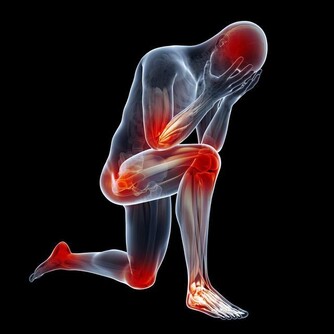

4、骨骼強壯。

中醫認為,腎主骨,骨靠腎精滋養,腎好骨才好。腎氣衰敗會出現骨質疏鬆、腰酸背痛,甚至牙齒出現鬆動。